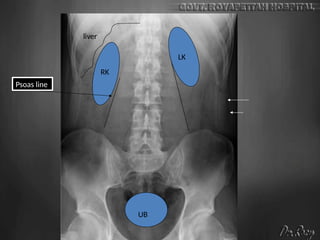

Abdomen

checklist

• Exposure

• Rotation

• Diaphragm + above and below

• Liver Spleen Kidney Psoas shadow

• Pelvis

• Calcification

• Abnormal bowel gas pattern / extraluminal air

• Soft tissue mass

• Visualized bones

liver

RK

LK

UB

Psoas line

Side

Marker

•NORMAL PLAIN X-RAY OF

•Normally the stomach and colon

contain gas that can show here,

particularly if the patient is not well

prepared

•Normally the small intestine

contains no gas (or a very minimal

amount). Small bowel gas shadow

may normally show in one or two

very small loops at most